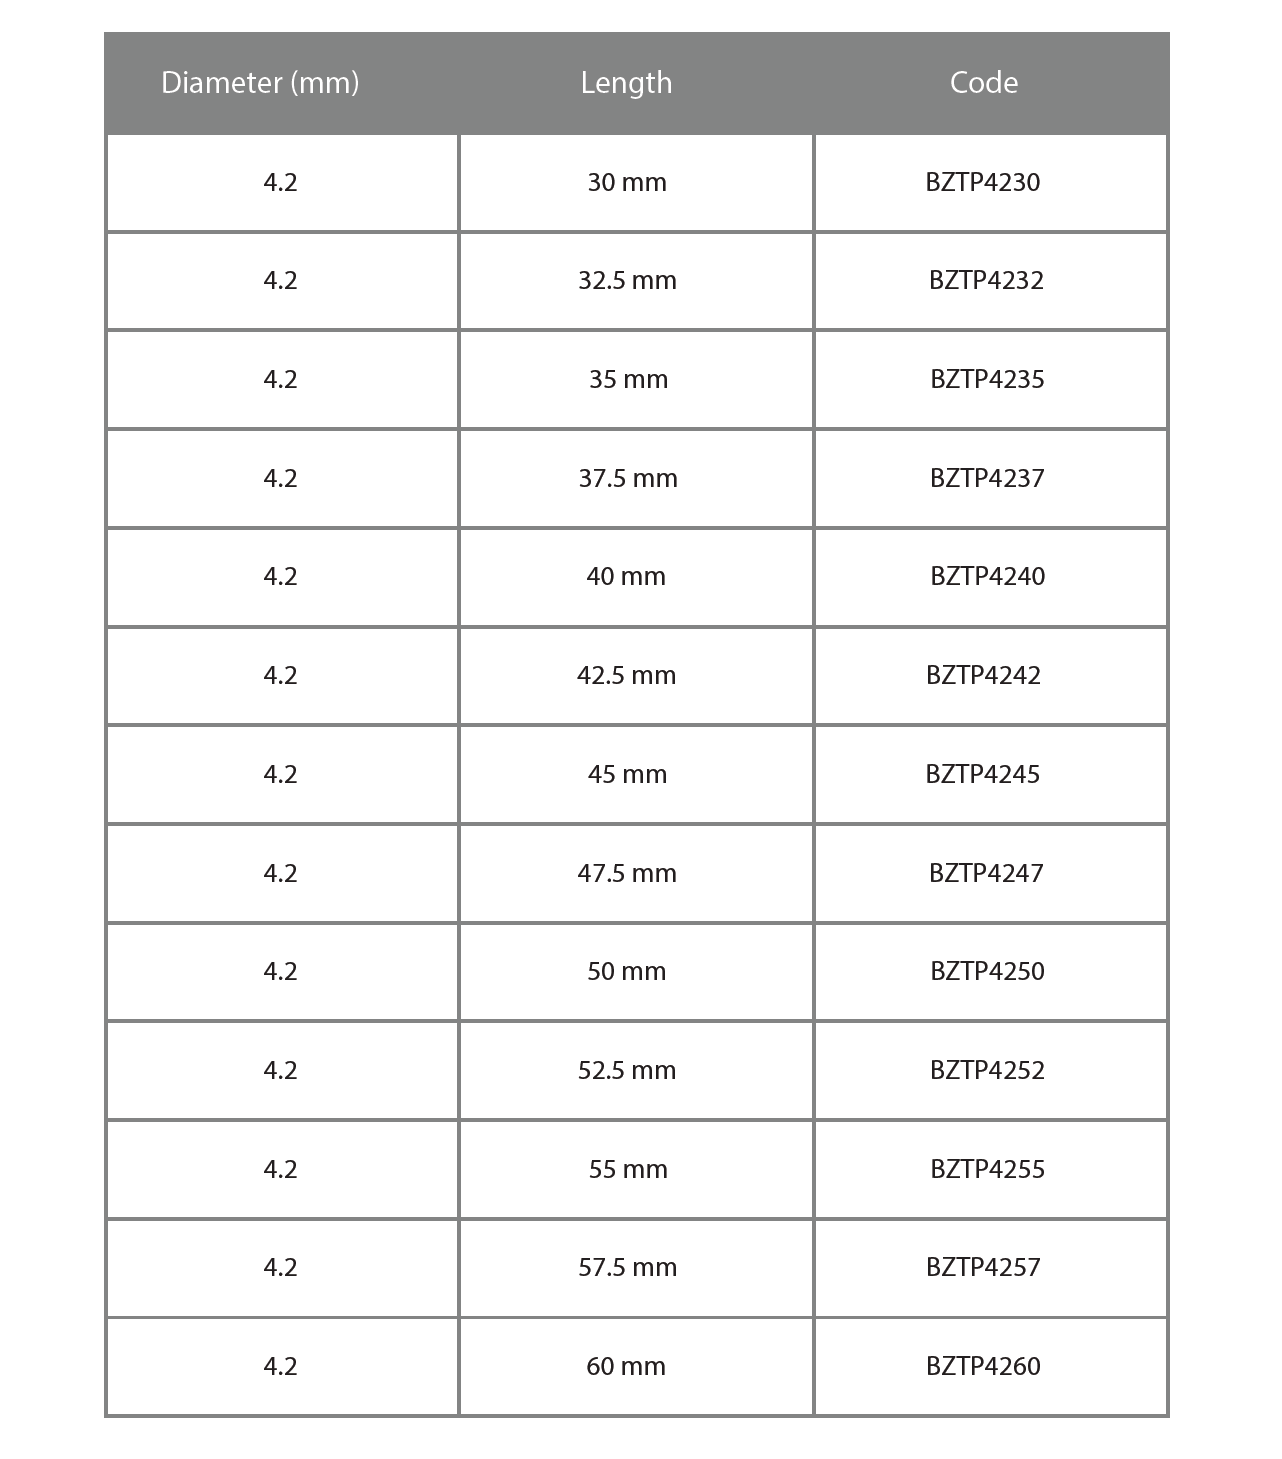

Measurement Information